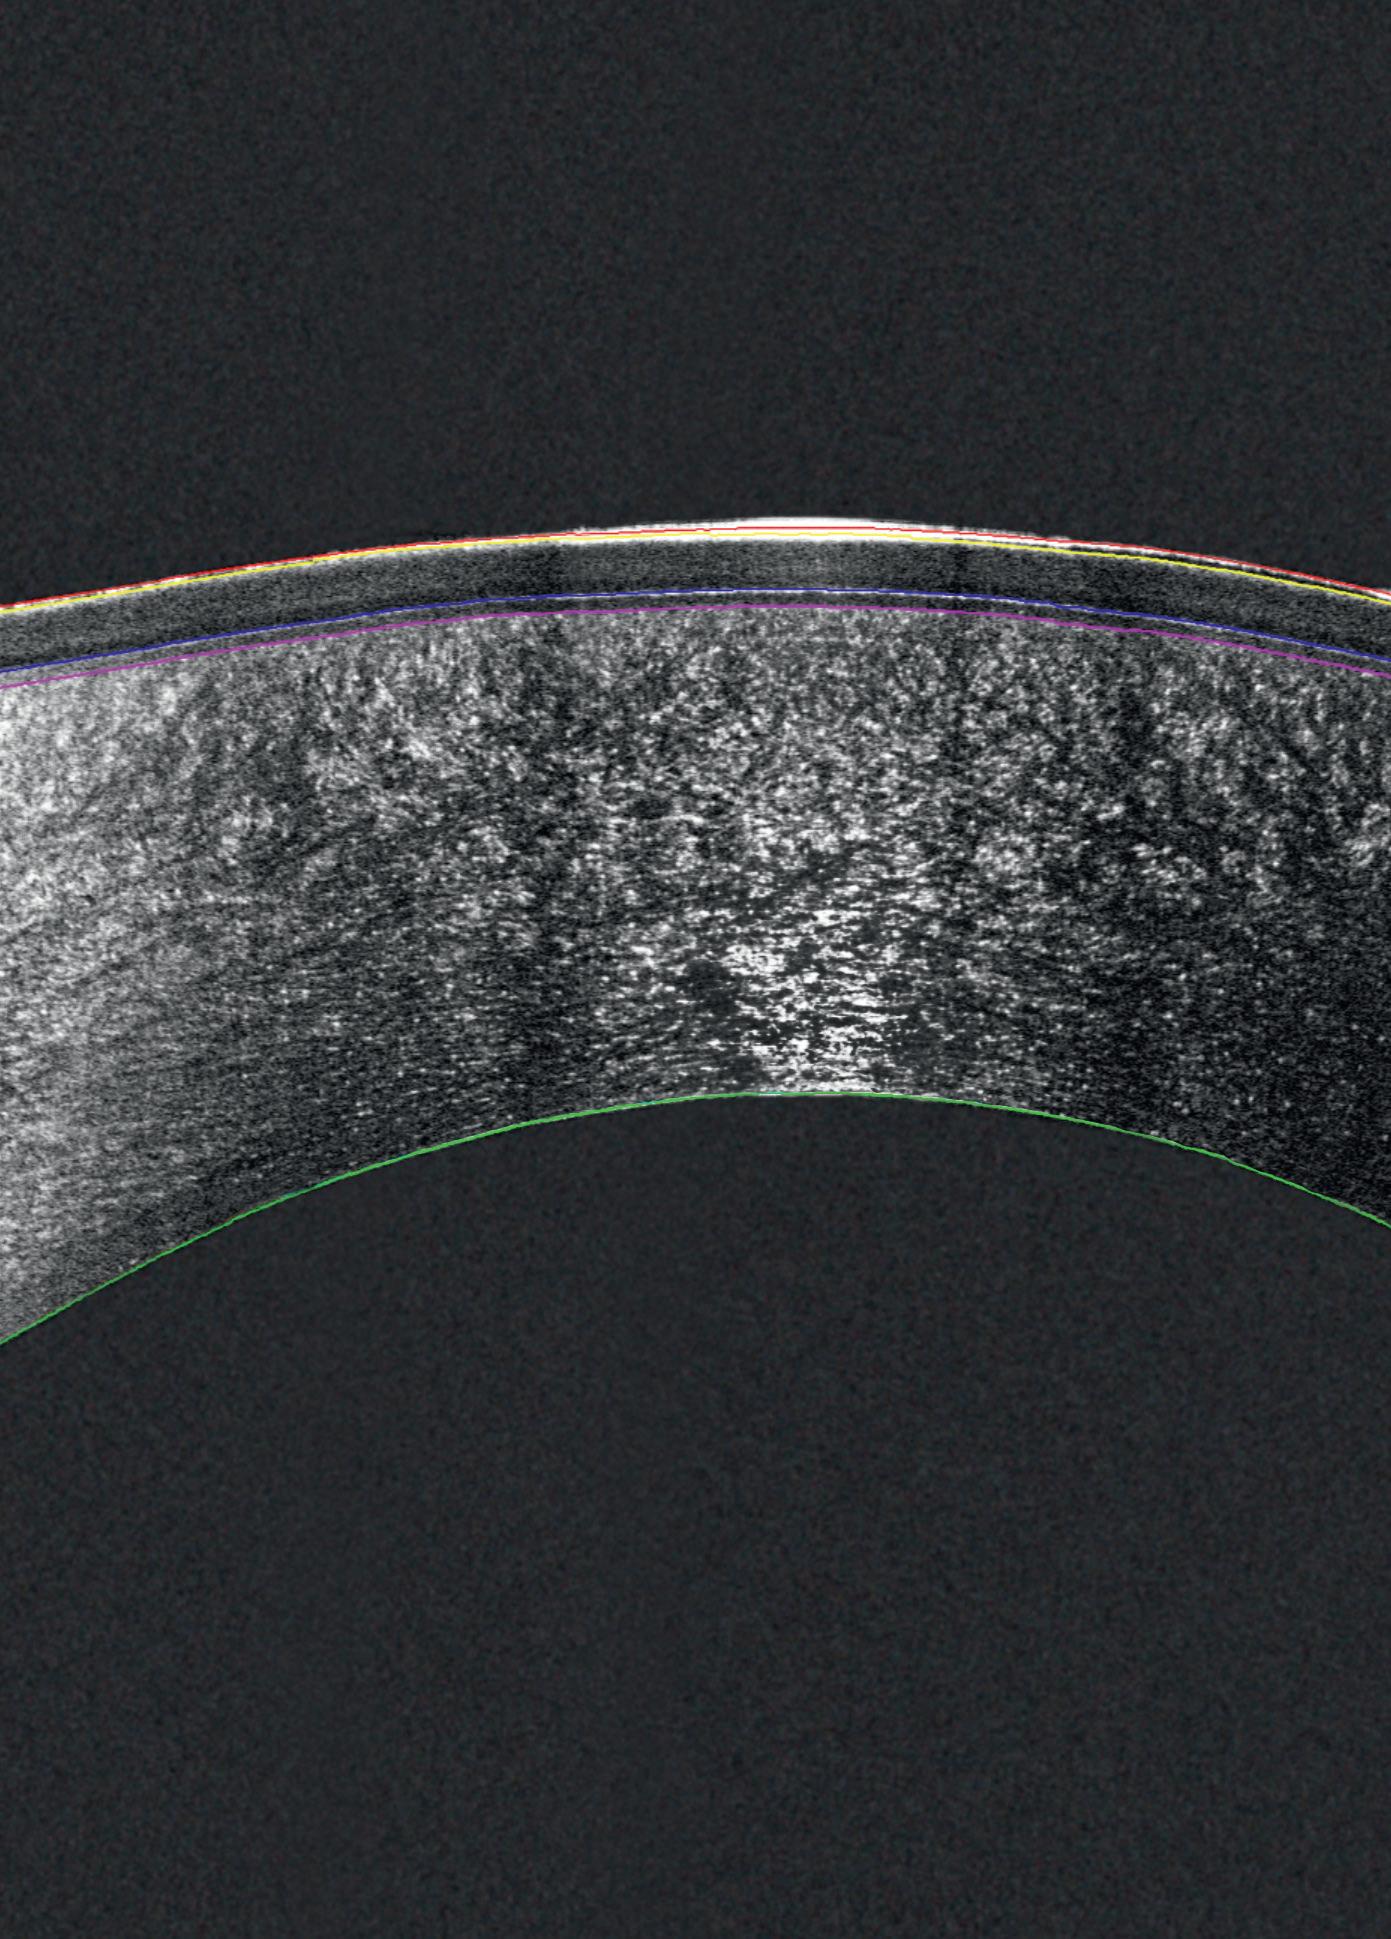

See the Unseen Experience Cornea Layer Segmentation

Detailed Sub-Layer Assessment

Combining the proven power of Scheimpflug imaging with the precision of ultra high-resolution OCT enables the detection of previously unseen corneal pathologies with unprecedented clarity.

Diagnose earlier. Treat smarter. Care deeper.

TEAR FILM

EPITHELIUM

BOWMAN’S LAYER

STROMAL LAYER

The Pentacam® Cornea OCT can increase the confidence that your diagnosis is correct.